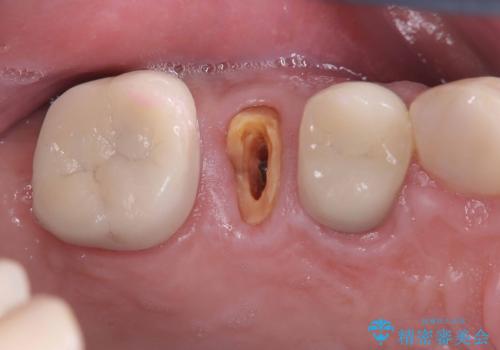

左上2番の大部分がプラスチックの材料で治療されていました。そのプラスチックの材料が劣化して変色し虫歯になっている状態でした。なので古いプラスチックの材料を全て除去し、その下の虫歯を取った後、オールセラミッククラウンで治療を行いました。オールセラミッククラウンを装着する前に当院にてホワイトニングを行いました。